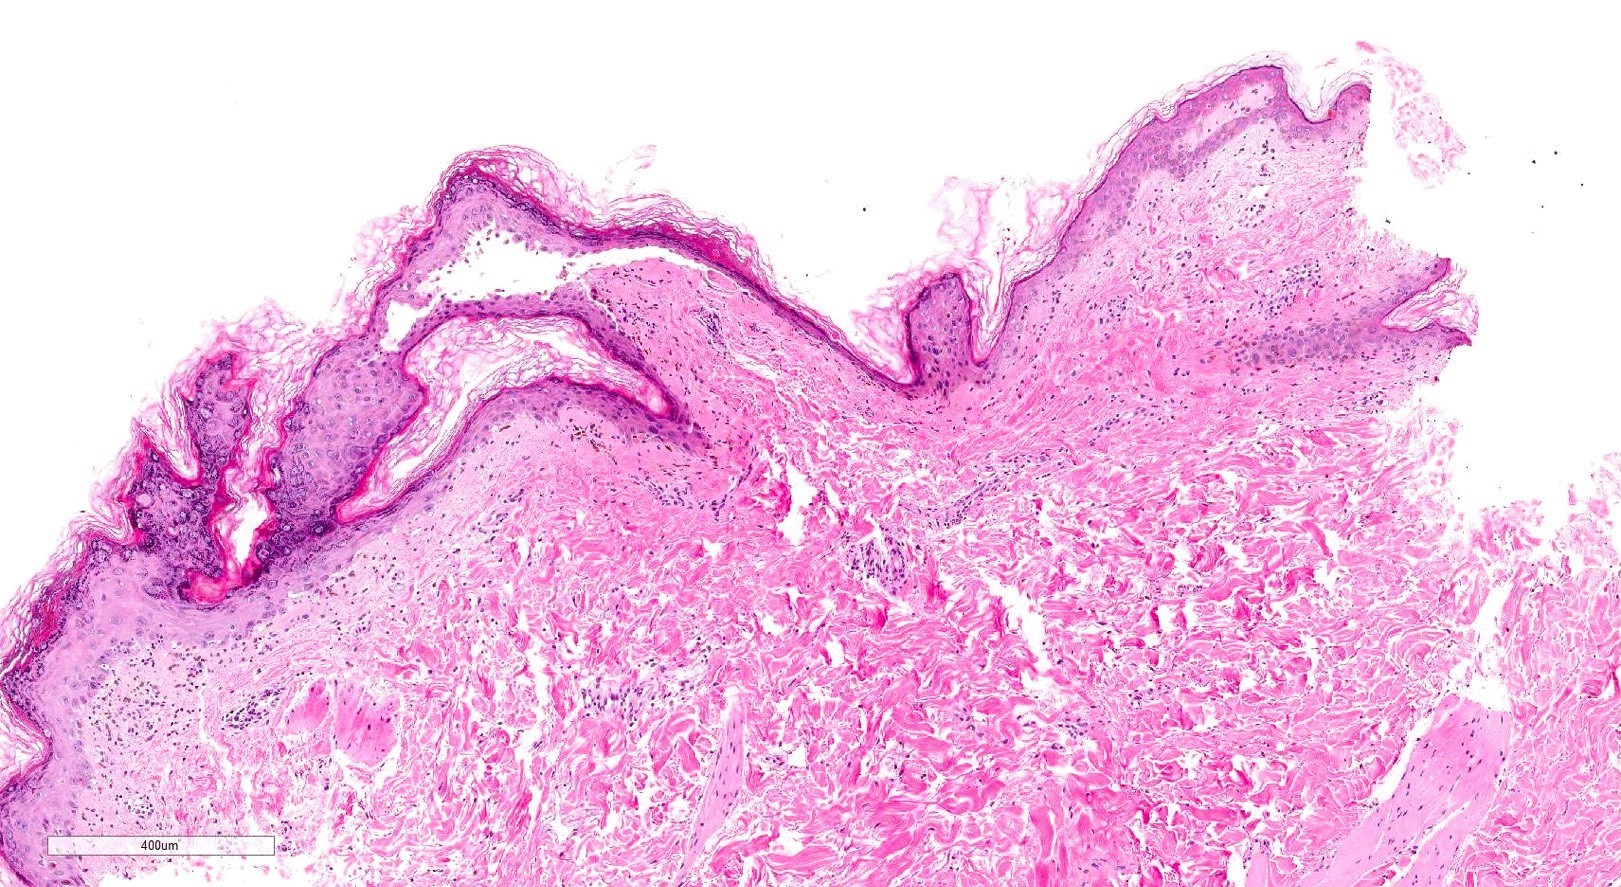

- Chronic GVHD (Biol Blood Marrow Transplant 2015;21:589, Patterson: Weedon's Skin Pathology, 4th Edition, 2015)

- Chronic lichenoid GVHD

- Acanthosis, orthohyperkeratosis, parakeratosis with hypergranulosis

- Underlying band-like lymphocytic infiltrate with basal layer vacuolization and apoptotic keratinocytes

- Periadnexal inflammation can be present

- May be difficult to distinguish from lichen planus without clinicopathologic correlation; satellite cell necrosis is the most helpful clue in GVHD biopsies to distinguish it from lichen planus

- Chronic sclerodermoid GVHD

- Dermal sclerosis (thickened compact collagen with loss of periadnexal fat)

- Manifests with localized morphea-like features, diffuse sclerosis or lichen sclerosus-like features

- Localized morphea-like features and diffuse sclerosis are largely confined to the reticular dermis or subcutaneous septa with little or no epidermal involvement

- Lichen sclerosus-like GVHD: collagen alteration is confined to the papillary dermis (hyalinzation of the papillary dermis), often with residual interface changes characterized by the presence of mild vacuolar alteration, melanophages and sparse superficial perivascular lymphocytic infiltrate

- In the fasciitis variant, biopsy specimens show only fibrous thickening of the fascia with adjacent inflammation without epidermal or dermal involvement

- Chronic lichenoid GVHD

Microscopic (histologic) images

Contributed by Silvija P. Gottesman, M.D. and Ohoud Aljarbou, M.D.